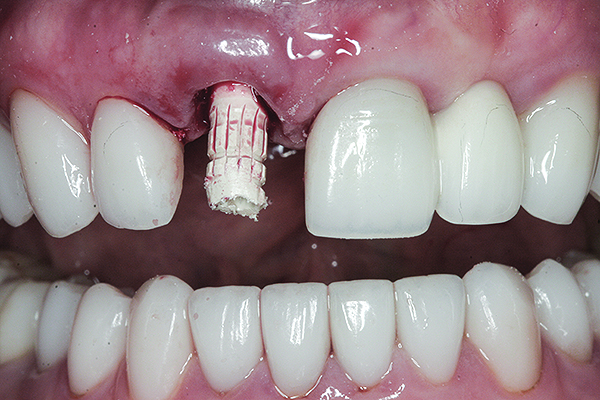

A cover screw was placed on the implant, and a combination of allograft/xenograft was inserted into the gap between the implant and the osteotomy (Figure 8). A temporary cylinder (PreFormance® Temporary Cylinder, BIOMET 3i) was then placed into the implant and modified (Figure 9). The screw-access opening was blocked out. A preoperative polyvinylsiloxane (PVS) impression was filled with bis-GMA resin (Luxatemp®, DMG America, www.dmg-america.com) and inserted over the modified temporary cylinder (Figure 10). This was allowed to set for 2 minutes. The screw was removed, and the temporary cylinder and provisional crown were removed from the mouth. A healing abutment (EP® Healing Abutment, BIOMET 3i) was placed into the implant and hand-tightened to support the peri-implant soft tissue while the provisional restoration was being modified extraorally.

Fig 9. The modified temporary cylinder in position.

Figure 9